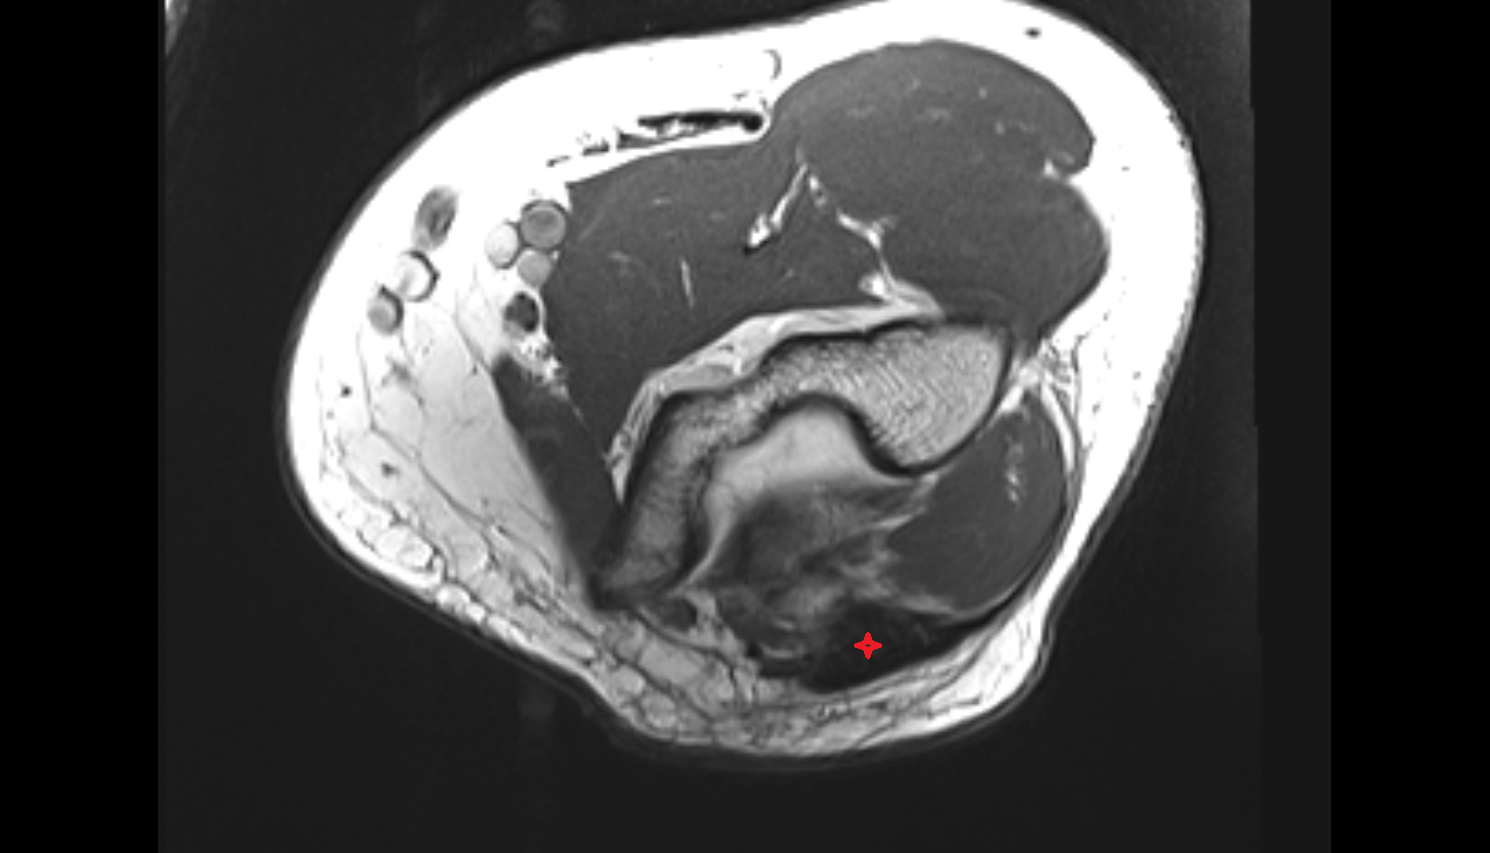

- Knee Joint

- Infrapatellar fat pad